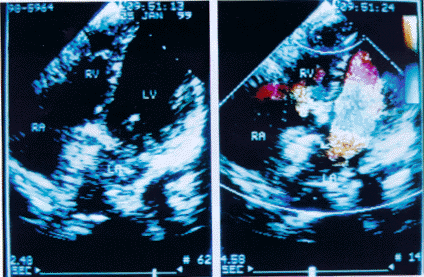

术后即刻和远期监测 本组5例手术成功的患者在行Amplatzer闭合器修补术中及第二天经胸超声心动图检查均无残余分流(图2),二尖瓣的形态活动亦不受影响。其中2例3个月后经胸超声心动图复查仍无残余分流。肺动脉收缩压降至正常(<30mmHg),无血栓形成及闭合器散脱等并发症。

左图示Amplatzer闭合器修补术后胸骨旁四腔心切面;

右图示Amplatzer闭合器修补术后彩色血流显像无残余分流

图2 Amplatzer闭合器修补房间隔缺损术后经胸超声显像。